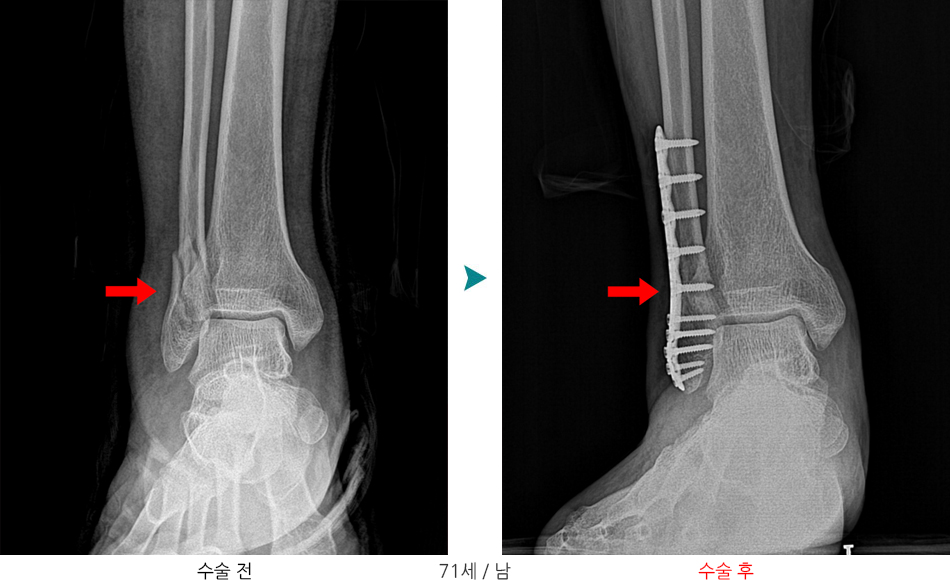

불안정성 골절, 전위가 큰 경우

- 금속판(plate), 나사(screw) 고정